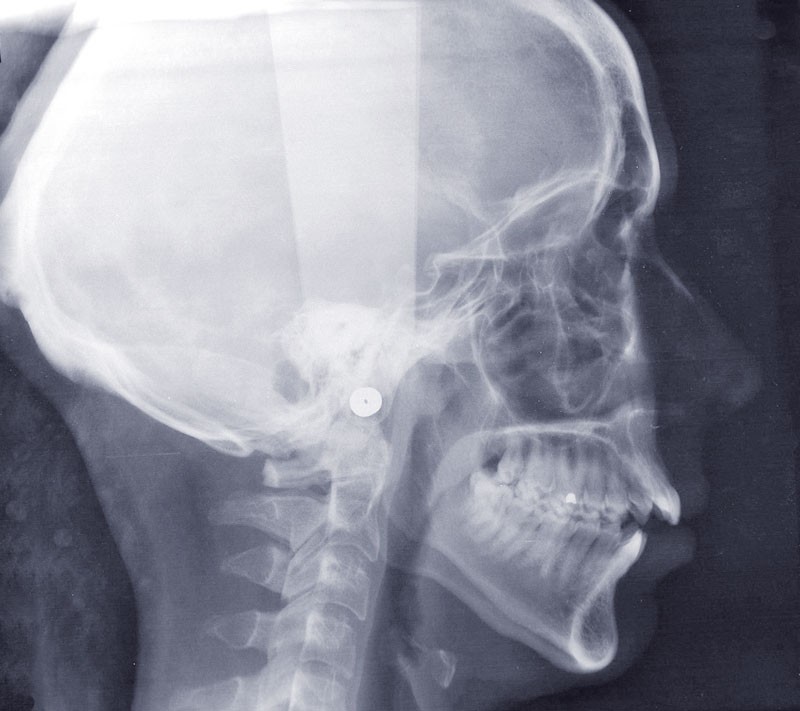

Diagnostic (fig. 1)

Cette patiente de 29 ans consulte pour des raisons principalement fonctionnelles mais également esthétiques. Elle présente :

– une classe II squelettique hyperdivergente

– une endognathie maxillaire

– une classe II division 1 majeure et asymétrique associée à une béance antérieure sévère

– un profil très convexe avec une occlusion labiale difficile et une biprochéilie

– une DDM par défaut modérée, maxillaire et mandibulaire

– des troubles de la posture et de la fonction linguale.